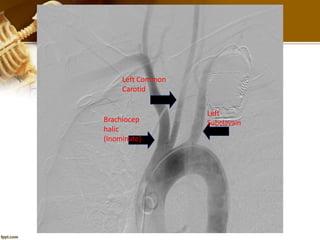

Brachiocep

halic

(Inominate)

Left Common

Carotid

Left

Subclavain